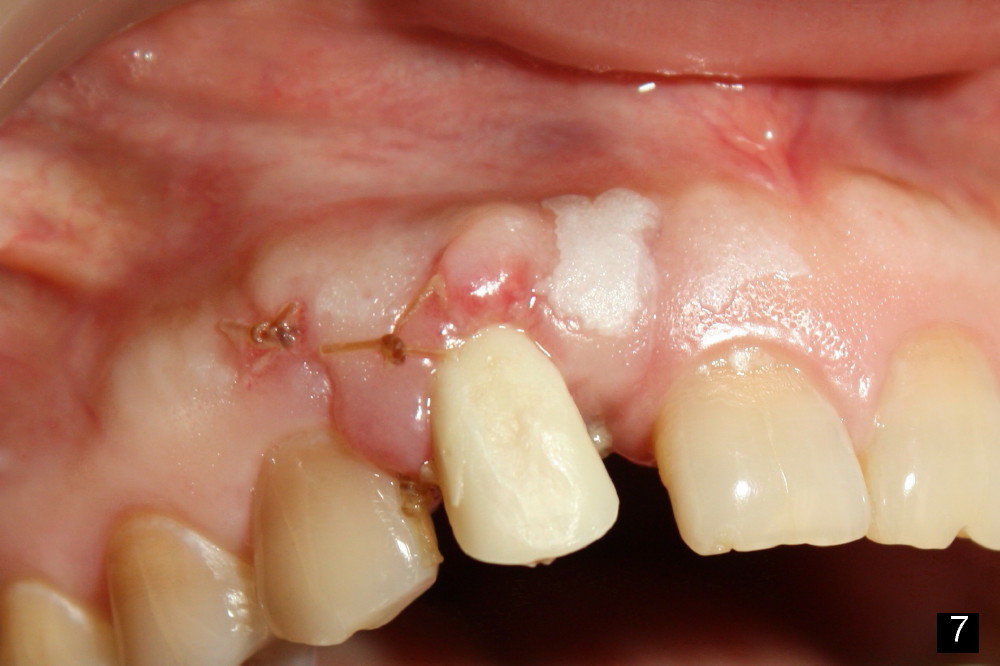

Fig.7,8 show the provisional 10 days and 1.5 months postop, respectively. When the provisional is removed, the implant/abutment is buccally malpostioned (Fig.9). It appears that segmental osteotomy is necessary. Fig.10 shows incision design. The implant and bone complex is to be moved to an ideal position (Fig.11,12). A block graft is inserted apically for internal fixation. An ortho wire is used for external fixation.